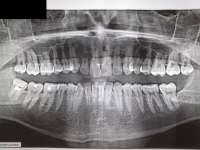

14872771621560.jpg (137Кб, 1280x841)

Кто может расшифровать? Почему пишут что все в пределах нормы, но постоянные звоны в ушах внезапные, вспышки. Азбука морзе в правом ухе в полной тишине.

>>575206

Пентоксифиллин первую неделю 100 мг утром и днём, вторую неделю 200 мг утром и днём, пить месяц-полтора в таком режиме, бетагистин первую неделю по 8 мг утром, днём и вечером первую неделю, вторую по 16 мг, пропить месяц-полтора в таком режиме; винпоцетин по 5 мг 3 раза в день месяц-полтора;

Не будет эффекта на третьей неделе, можно будет добавить пирацетам по 400 мг утром и днём (в первую неделю), а потом и по 800 мг утром и днём, пропить месяц-полтора; а также никотиновую кислоту по четвертинке от таблетки в 50 мг, утром, днём и вечером 2-3 недели.

РЭГ вообще так себе исследование, честно говоря, оно слабо информативное. Но судя по тому, что тут указано, диагноз может звучать как "вертебро-базилярная недостаточность". Оттого (ну или опосредованно) и тиннитус.

Я предложил сосудорасширяющую терапию, которую тебе предложит любой другой врач. С антидепрессантами там все сочетается в принципе, противопоказаний нет.